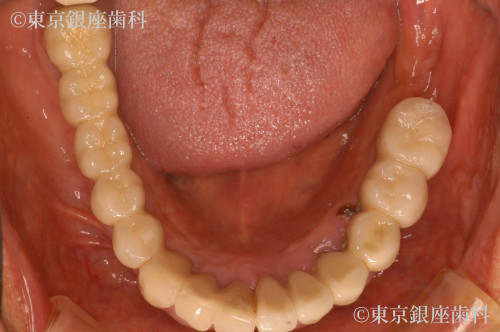

After

奥歯上下をインプラント治療

奥歯は延長ブリッジ